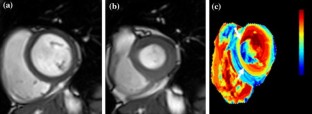

Figure 3

Part of this figure is modified, with permission, from Ref. 8.